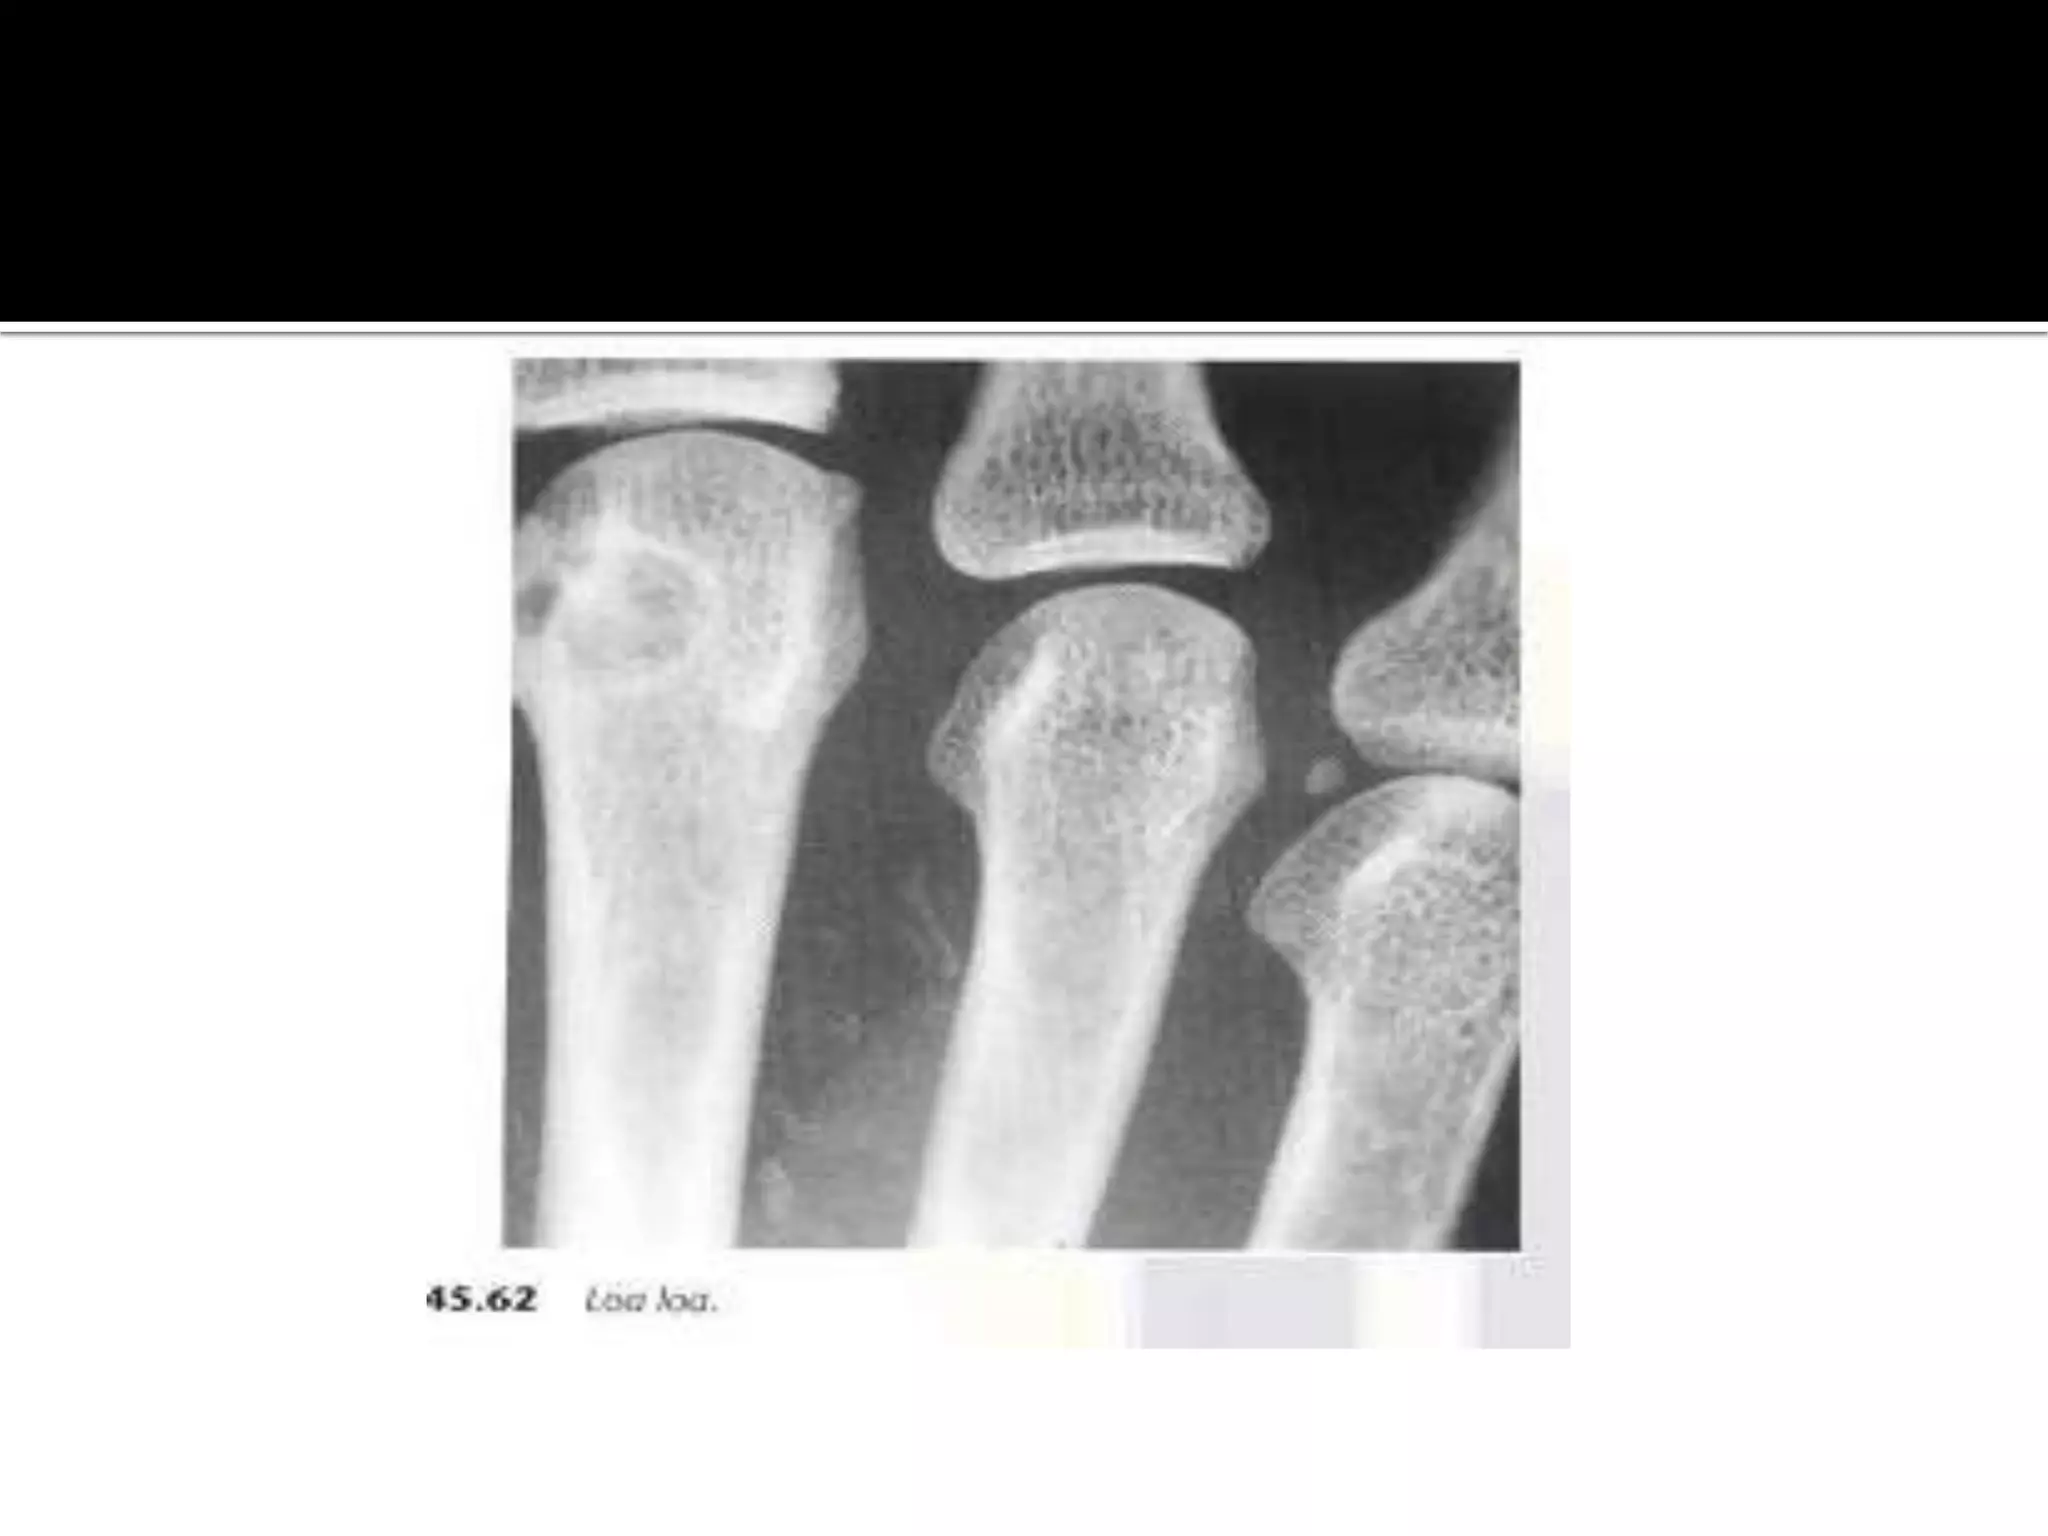

 Loa loa or micro filariasis ,is a small parasite which is

common in west Africa. it dies and calcifies

appearing as coiled threads in the hands and feet.

 Loa loaor micro filariasis ,is a small parasite which is common in west Africa. it dies and calcifies appearing as coiled threads in the hands and feet.  Armillilifer arnillatus is a parasite which infest snakes and infects human who eat them. it appears as C-shaped calcifications less than 1 cm in length in the serosa of the chest and abdomen.